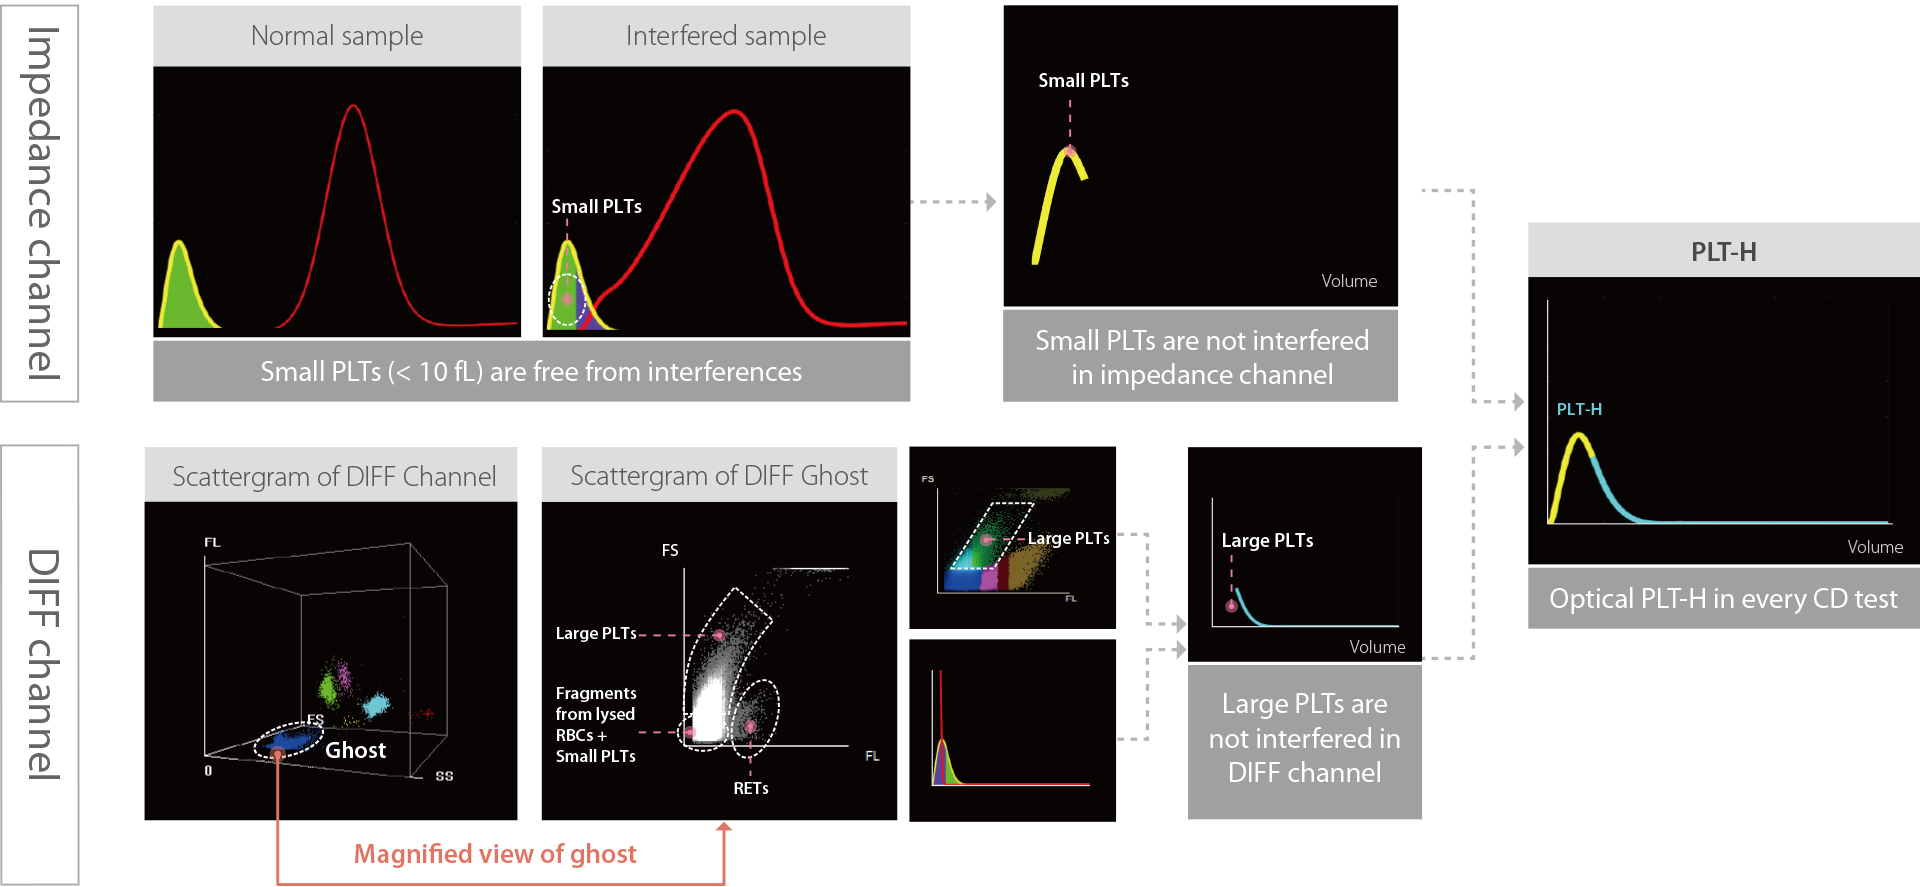

Comprehensive Solution for Accurate PLT Results

Brand new PLT-H in every CD test

PLT-O with Multiple Counting for Low-count Platelet

There is no need to re-aspirate samples. The instrument will automatically conduct 8 times statistical analysis on low PLT count samples to improve the detection accuracy.

Scattergram before and after Auto 8x PLT-O counting

PLT-O with automated PLT-clumps de-aggreation technology

It solves the problem of falsely low PLT count samples caused by EDTA induced pseudo-thrombocytopenia.

Automatic retraction and re-testing with PLT-O